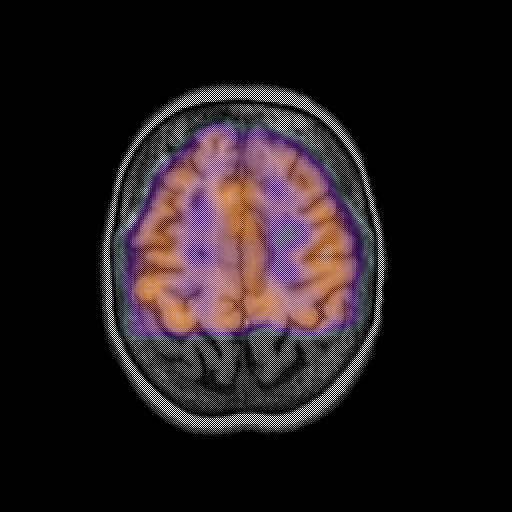

overlay: Slice 40

Slice 40

MRCBFCBF with

T1PDT2T1PDT2